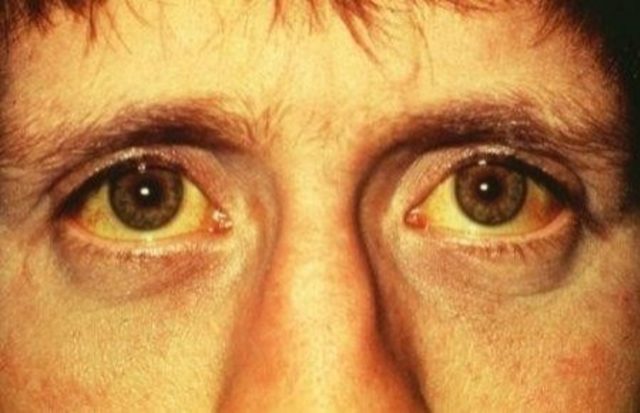

Emrullah taşındı görüntülü yanıtlıyor. Doğduğumda sararmışım ondan kalmış. Birincigöz hastanesi op dr fuat karakaya göz akı sararması ile ilgili bilgilendiriyor.

Göz akının sararması. Yani vücutta tene rengini veren göz zarında da bulunan melanin pigmenti miktarı artarsa göz akında sararmalar görülebilir. Havuç ıspanak lahana portakal ve sarı renkli meyvelerdir. Kan bilindiği gibi pek çok farklı maddeden oluşmakta ve bu maddelerden biri olan biliruibinin fazlalığı halinde gözde sararma meydana gelmektedir. Göz akının sararması neden olur.

Hepatitler safra yolları ve safra kesesi tümörleri safra kesesi taşları göz aklarının ve cildin limon gibi sararmasına sebep oluyor. En iyi a vitamini kaynağı bitkiler. Benim göz beyazlarım biraz sarı. Göz akı sararması için kullanılacak göz akı beyazlatmada faydalı bitkiler a vitamini içeren bitkilerdir.

Genel olarak tek başında görülmeyen bir durum olan göz akı sararması bir hastalığım belirtisi olarak bizleri uyarmaktadır. Aslında sarılık hastalık değil birçok durumda ortaya çıkabilen bir belirtidir. Zamanla güneş ışınlarının etkisi ile de sklerada melanin pigmenti birikmesi ile oluşur. Fakat melanin miktarı fazla artıp ben oluşumuna neden de olabilir.

Kanda bilüribin denilen bir maddenin artması nedeniyle göz ve cildin sararmasıdır. Göz akında oluşan sararma fizyolojik olabileceği gibi patolojik de olabilir. Bir doktor enzim eksikliğinden dedi. Göz akının sararması merhaba hocam gözlerimin akı öncelere göre sarardı bembeyaz durmuyor bu durum beni rahatsız ettiğinden birkaç kez doktora gittim ancak her seferinde 15 günden fazla kullanmamamı söylediği damlalar verdi.